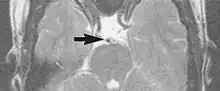

A motion artifact is one of the most common artifacts in MR imaging.[2] Motion can cause either ghost images or diffuse image noise in the phase-encoding direction. The reason for mainly affecting data sampling in the phase-encoding direction is the significant difference in the time of acquisition in the frequency- and phase-encoding directions.[1] Frequency-encoding sampling in all the rows of the matrix (128, 256 or 512) takes place during a single echo (milliseconds). Phase-encoded sampling takes several seconds, or even minutes, owing to the collection of all the k-space lines to enable Fourier analysis. Major physiological movements are of millisecond to seconds duration and thus too slow to affect frequency-encoded sampling, but they have a pronounced effect in the phase-encoding direction. Periodic movements such as cardiac movement and blood vessel or CSF pulsation cause ghost images, while non-periodic movement causes diffuse image noise (Fig. 1). Ghost image intensity increases with amplitude of movement and the signal intensity from the moving tissue. Several methods can be used to reduce motion artifacts, including patient immobilisation, cardiac and respiratory gating, signal suppression of the tissue causing the artifact, choosing the shorter dimension of the matrix as the phase-encoding direction, view-ordering or phase-reordering methods and swapping phase and frequency-encoding directions to move the artifact out of the field of interest.[1]